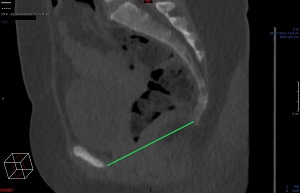

Tunna snitt-serien sagittalt i Power Viewern ("MPR"), snittjocklek 7-10 mm, skelettfönster. Scrolla fram till symfysens mitt. Mät det kortaste avståndet mellan symfysens kraniala-dorsala omfång och sacrums kraniala-ventrala omfång.